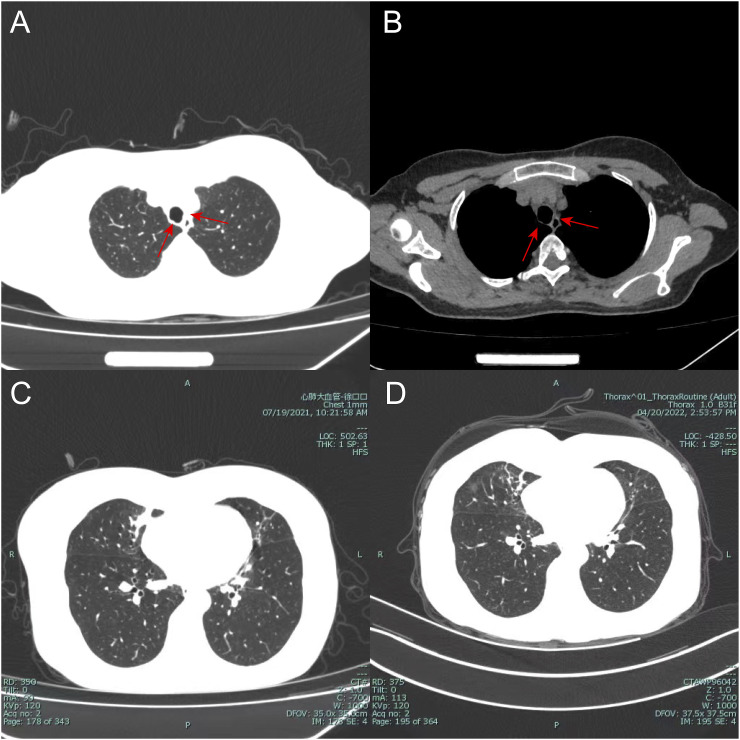

A 57-year-old female presented with a chief complaint of cough, with productive yellow sputum particularly severe in the morning. Bronchoscopy revealed inflammatory changes in both main bronchi, with abundant white purulent secretions and necrotic material adhering to the luminal surface. Histopathological examination showed chronic inflammatory changes in the mucosal tissue, with mild hyperplasia of the local squamous epithelium and evidence of keratinization in the surrounding area, consistent with a diagnosis of tracheal mucosal keratosis. The patient was treated with anti-infection therapy, combined with symptomatic supportive treatments such as cough suppression, expectorants, and bronchodilation, resulting in an improvement of symptoms. Analysis of previous literature revealed that although this condition lacks specific clinical manifestations and signs, it exhibits a typical pattern of tracheal wall lesions, and bronchoscopy and histopathological examination have high diagnostic value for this disease. Due to impaired airway mucosal barrier function, the patient is prone to bacterial infection or colonization in the airways. Symptomatic supportive treatment based on the actual condition can effectively alleviate the patient's clinical symptoms. Currently, there is no definitive curative treatment for tracheal mucosal keratosis. However, treatments such as high-frequency electrocautery, carbon dioxide cryotherapy, and repeated lavage with epidermal growth factors may be helpful in curing this condition.